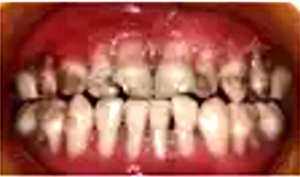

口腔??茩z查:口腔黏膜光滑,全口唇頰側(cè)牙齦重度萎縮,牙根暴露,探診易出血,牙齒表面可見齲壞及色素沉著,口腔衛(wèi)生可。遠(yuǎn)中切角缺損,Ⅱ度松動(dòng),唇側(cè)牙齦萎縮至根中1/3伴腫脹;Ⅱ度松動(dòng),唇側(cè)牙齦萎縮至根中1/3伴腫脹;冠完整,Ⅲ度松動(dòng),唇側(cè)牙齦萎縮至根尖1/3,齦乳頭及舌側(cè)牙齦萎縮程度較唇側(cè)輕(圖1)。

圖1 重型先天性中性粒細(xì)胞缺乏癥患者口內(nèi)照片